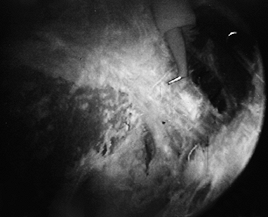

![]() |

Figure 79.10. Arthroscopic debridement of a partial-thickness undersurface tear.